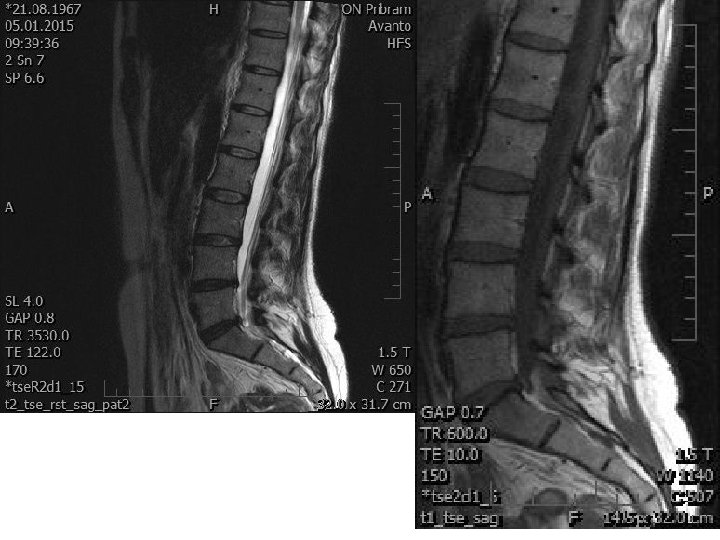

The MRI images from 1/2015 the lumbar spine in the area L 4/5 there is disc protrusion broad-based medial to right paramedial, the width is about 4 mm and it is in the small cracks in the annulus fibrosus, on the both sides. The deck L 5/S 1 is a broadbased disc protrusion paramedian on the right only 2 mm width, minimally overlapping and mutually to the foraminal space. Significant improvement.